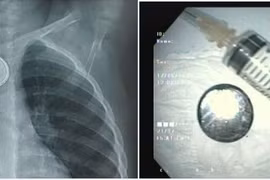

Cứu bé trai gần 3 tuổi nuốt pin cúc áo loét thực quản

Một bé trai gần 3 tuổi nuốt phải pin cúc áo gây loét thực quản, các bác sĩ cảnh báo tổn thương nguy hiểm khi nuốt phải pin.